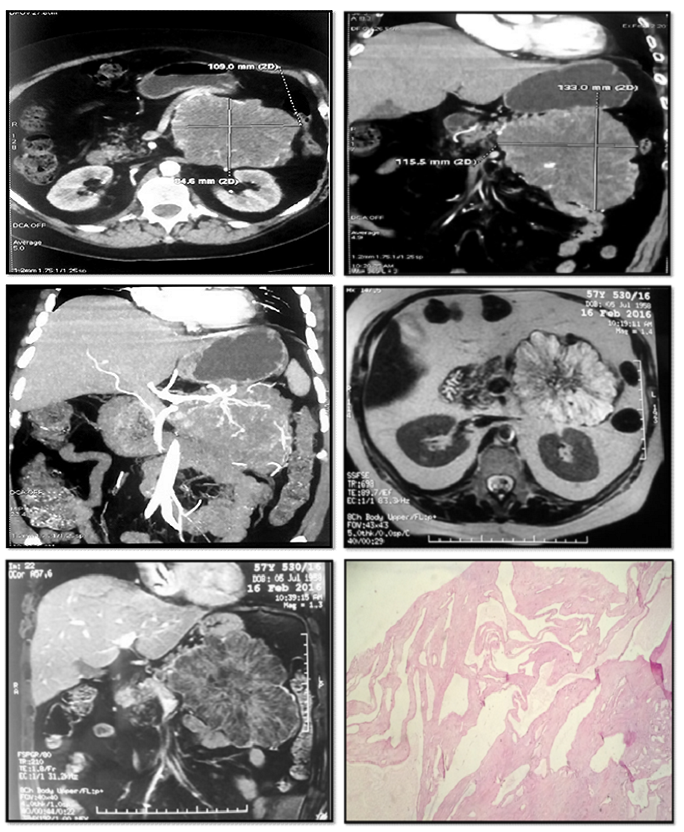

Cystic Lymphangioma of the Pancreas: About A Case and Literature Review

Dr Kouassi Armel Serge Kouame, Dr Aboulfeth El Mehdi, Dr Bouzroud Mohamed, Pr Najih Mohamed, Pr Kaoui Hakim, Pr Bounaim Ahmed

International Journal of Innovative Research in Medical Science·August 1, 2021